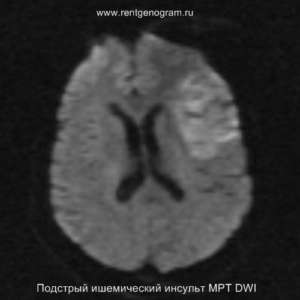

На МРТ и КТ изменения могут отсутствовать. На МРТ у некоторых пациентов могут быть первые признаки ишемии. На DWI область ишемического повреждения может быть видна через 2,5 часа после появления первых симптомов.

С 4-5 часов на DWI должны быть заметны признаки ишемического поражения, которые представляют собой «ядро» инфаркта.

Острая фаза (6 — 24 часа)

В течение острого этапа на МРТ и КТ выявляются все морфологические признаки ишемического инсульта. Область острого ишемического инфаркта визуализируется как зона ↑Т2, ↑Flair, ↑DWI и ↓Т1 ↓ADC. Можно обнаружить тромб в артерии. На КТ в остром этапе также чётко дифференцируется поражённая область, представляющая собой участок с потерей дифференциации мозговых структур и снижением их плотности. Контрастирование в остром периоде не показывает патологических участков с накоплением контраста.